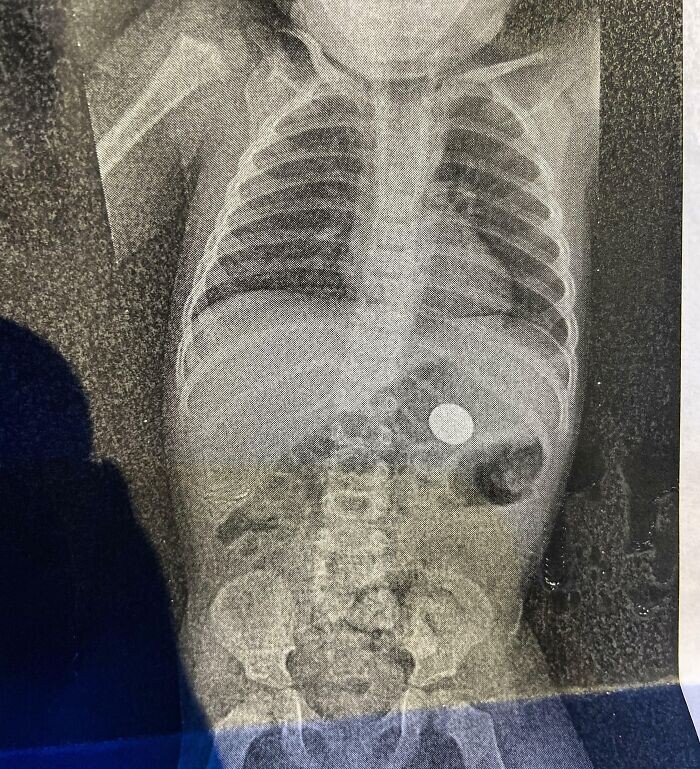

2. "В День святого Валентина мой сын решил показать мне свой первый магический трюк: как заставить монету исчезнуть. Рентген спустя я нашла её"